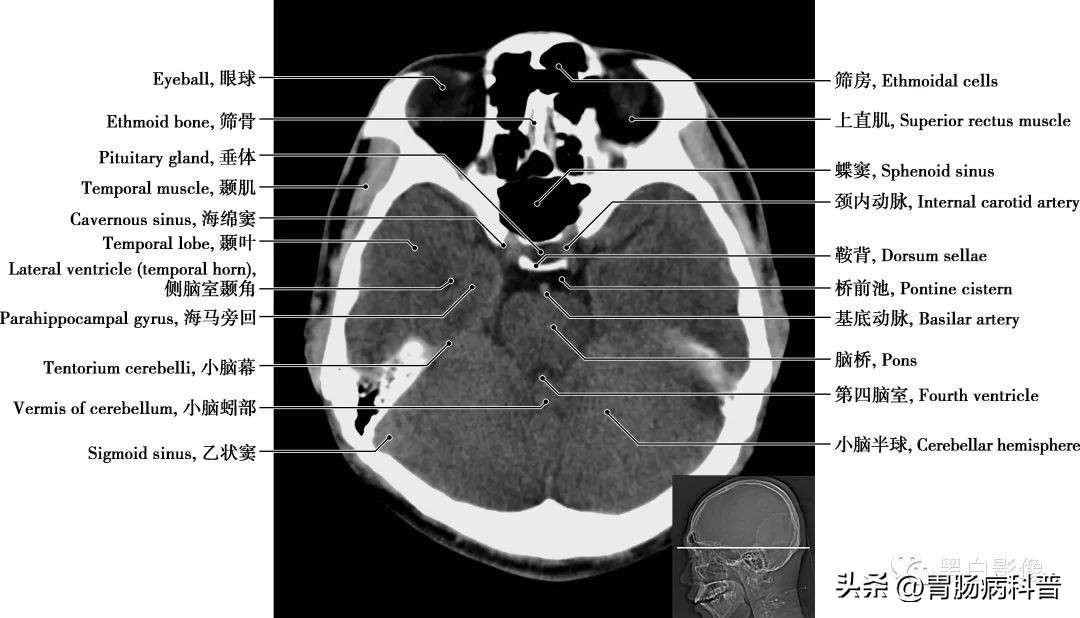

图1-1-13 经海绵窦轴位切面

垂体 位于下丘脑的腹侧,为一卵圆形小体。分为腺垂体,包括远侧部、结节部和中间部;神经垂体由神经部和漏斗部组成,神经垂体较小,由第三脑室底向下突出形成。垂体分泌多种激素,如生长激素、促甲状腺激素、促肾上腺皮质激素、促性腺素、催产素、催乳素、黑色细胞刺激素等,还能够贮藏下丘脑分泌的抗利尿激素